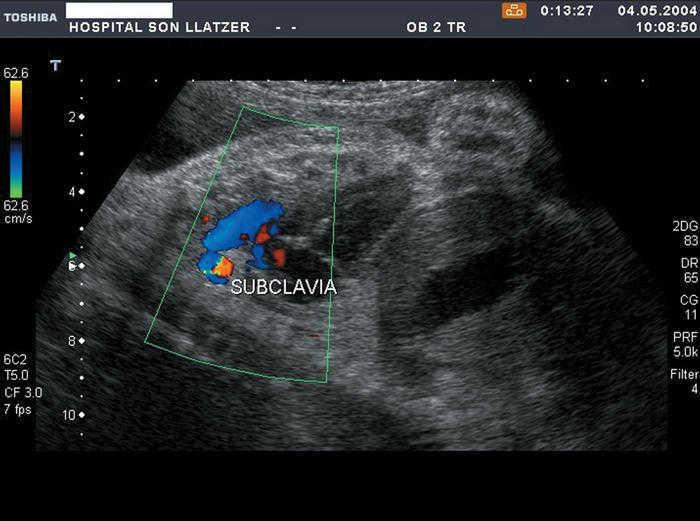

Si se utiliza el Doppler color, se aprecia un flujo de sangre anterógrada en el ductus y un llenado retrógrado desde éste hacia la aorta descendente (fig. 1). Esta zona corresponde a la conocida como divertículo de Kommerell, descrito por Burckhard F. Kommerell en 193613. También se podrá visualizar el flujo retrógrado en un corte paraesternal longitudinal del ductus (fig. 5).

Figura 5.Cuando se observa el arco del ductus en un corte paraesternal longitudinal largo, se ve un flujo retrógrado que lleva sangre del ductus a la aorta (subclavia).